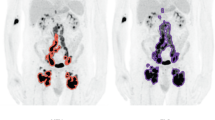

The TMTV were delimited in both software by a medical physicist and supervised and approved by a specialist nuclear medicine physician. Multiple physician supervision was not considered essential due to the use of automatic methods for localized lesions. To delimit TMTV with the BI software using a single region of interest (ROI), a ROI involving all focuses of [18F]FDG activity was drawn in one of the slices of each patient avoiding physiological uptake. Despite the difficulty of this procedure, since in many of the patients the injured region was at a different depth in the frontal axis than the physiological uptakes from the heart or lymph nodes, we were able to perform the analysis with precision by the definition of the single ROI in most of the cases. It was then extrapolated to the limiting slices obtaining a volume of interest (VOI) to which 2.5, 41% and 50% cut-offs were applied (Fig. 1). The software automatically selected and highlighted the voxels with a SUV value over the threshold and calculated the TMTV, SUVmean, SUVmax, and SUVpeak. Total lesion glycolysis (TLG) was later calculated for each threshold as the product of SUVmean and TMTV. The procedure for LIFEx was performed similarly but the ROIs were modified slice by slice, detecting only tumoral regions and avoiding physiological uptake healthy organs. The mentioned thresholds were applied to the defined VOI and the same parameters were calculated.

For the 2.5 cut-off, more significant differences between single and multiple procedures were found for BI (r = 0.9994, p = 0.07) than for LIFEx (r = 0.995, p = 0.33). Using BI, for 41% (r = 0.94, p = 0.04) and 50% (r = 0.98, p = 0.007) statistical significance between compared values was obtained, as well as for LIFEx (r = 0.92, p = 0.0004, and r = 0.96, p < 10–5, respectively). The highest correlations were found between LIFEx single ROI and BI multiple ROI (Fig. 3), showing the effect of the use of multiple ROI drawings in BI compared to single ROI drawings in both BI and LIFEx, respectively.